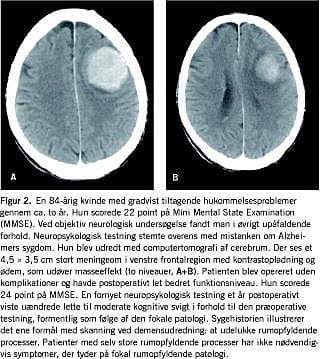

Sammenligner man forekomsten af operabel patologi i ÅS og RH på 4% med tidligere studier findes der god overenstemmelse mellem denne opgørelse og opgørelser fra andre demensklinik/ambulatoriebaserede studier, hvor forekomsten varierer mellem 1% og 4% [2, 3]. Disse studier viste - i overensstemmelse med dette studie - en forekomst af operable tilstande, hvor operation har hel eller delvis effekt på omkring 2% [2, 3]. Selv om påvisning af operabel patologi ikke medfører operation eller remission efter operation, har påvisningen dog betydning for information, rådgivning og behandling (Figur 2 ).